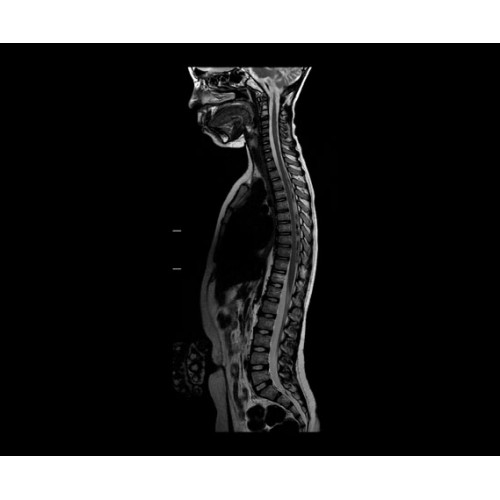

SIGNA PET/MR 3.0T — это гибридная система, в которой совмещаются две принципиально разные технологии — магнитно-резонансную томографию (МРТ) и позитронно-эмиссионную томографию (ПЭТ). Система отличающийся высокой чувствительностью и эффективностью и предназначена для диагностики в области онкологии, неврологии, кардио-васкулярных исследований, исследований воспалительных процессов.

Компания GE Healthcare представляет революционную, полностью интегрированную систему SIGNA PET/MR1, в которой сочетаются времяпролетная технология (TOF) и возможности напряженности магнитного поля 3.0 Тл. Мы поможем вам поднять исследования на более высокий уровень. SIGNA PET/MR позволяет достичь впечатляющей точности и скорости исследований, а благодаря новейшей технологии реконструкции Q.Clear2 качество изображений улучшается в два раза. Кроме того, в систему включен полный набор клинических приложений и гибких катушек для проведения любых видов исследования, открывая для вас возможности визуализации, о которых вы даже не догадывались.